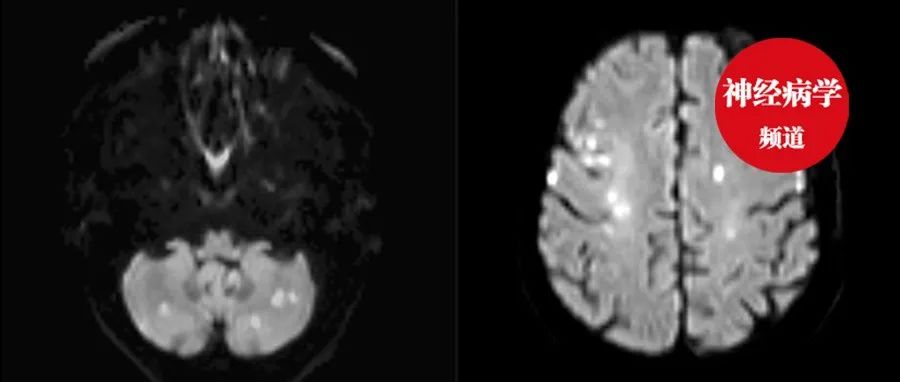

脑梗死抗凝后反复血栓形成,几天后死亡,这个病因太棘手......

*仅供医学专业人士阅读参考遇到这些症状,别忘了这个病因。 今天为大家介绍一例74岁女性因缺血性卒中住院,排除了常见的可能引起卒中的原因,发现患者同时存在其它器官的栓塞事件(高度提示高凝状态),经调查发现肺隐匿性肿瘤,病情迅速恶化,尽管进行了抗凝治疗,但仍出现反复栓塞事件,最终导致患者死亡[1]。希望能给诸位来带一定的收获。病例回顾74岁女性,“突发语言障碍、口角歪斜、右侧肢体乏力12小时”入院。...